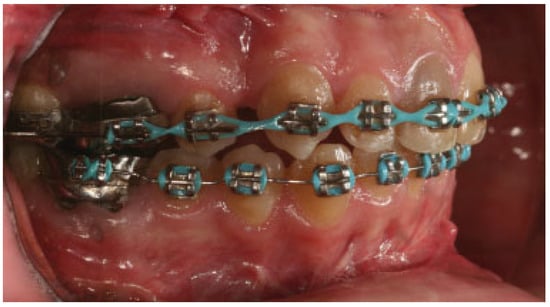

:Case Report